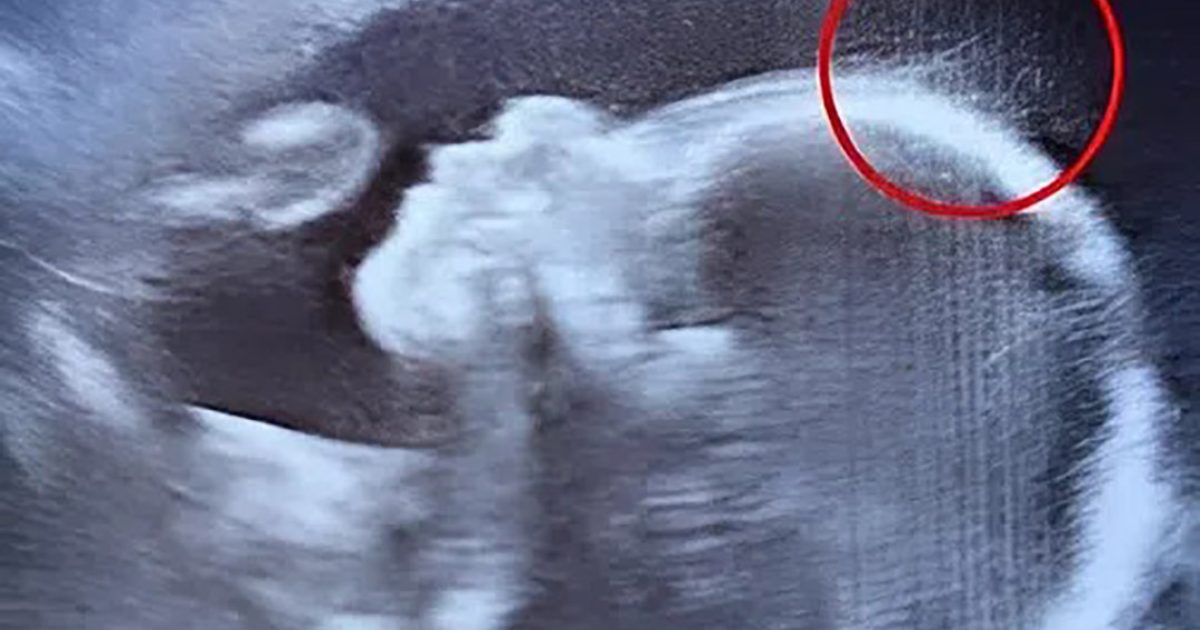

Le rapport préliminaire mentionnait une hémorragie post-partum. Une complication obstétricale bien connue, parfaitement traitable avec des soins appropriés. Mais sur place, elle avait été minimisée, étouffée par le poids d’une tradition appliquée rigidement.